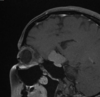

Esclerose mesial temporal

Observe a perda de volume, que indica atrofia e causa aumento secundário do corno temporal do ventrículo lateral.

O sinal alto no hipocampo reflete a gliose.